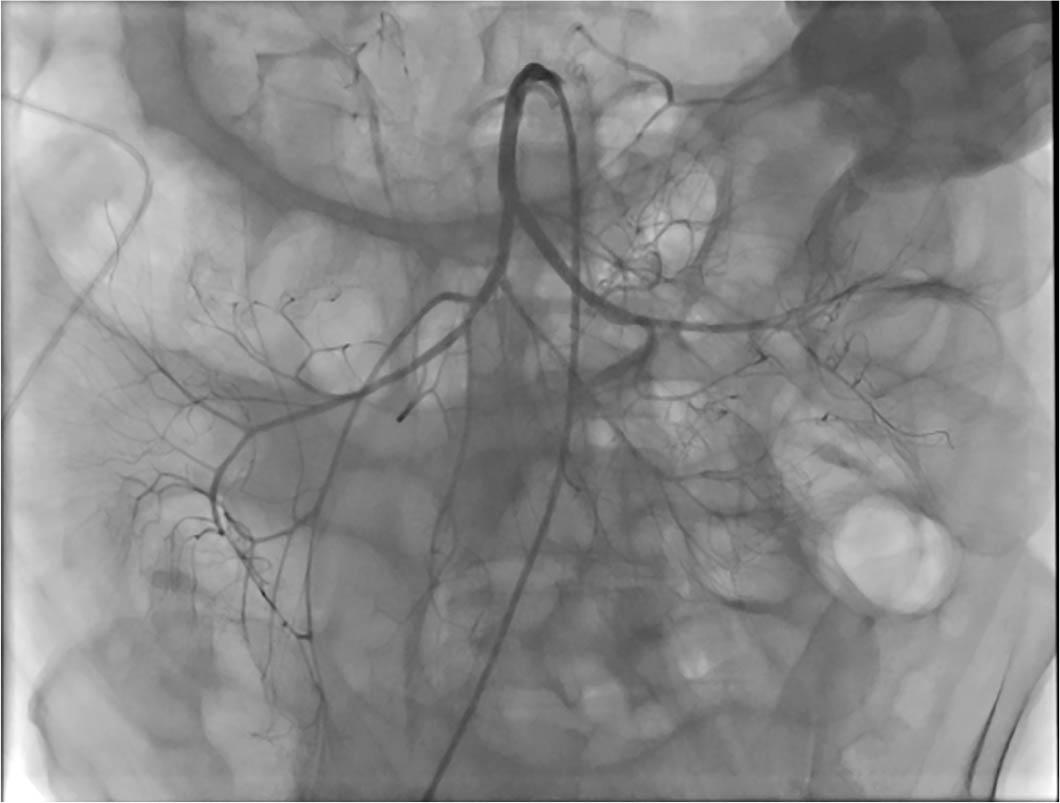

Figure 2